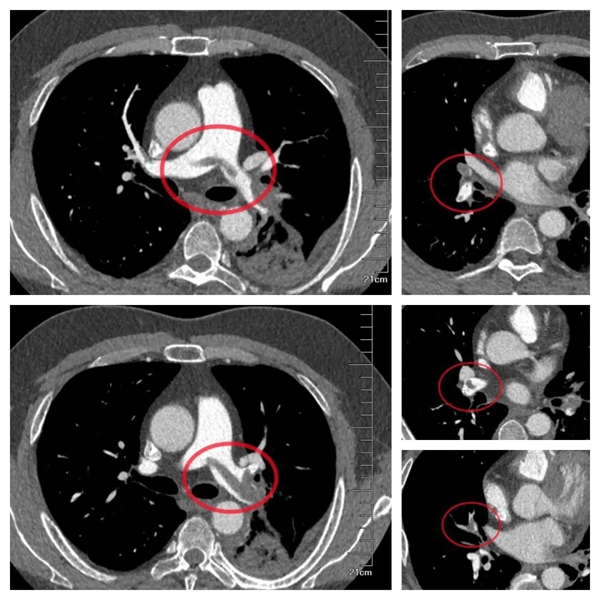

为明确诊断,医生迅速为小李安排下肢血管彩超检查,结果证实了担忧:右侧小腿肌肉内静脉附壁血栓,右下肢深静脉血栓形成,且血栓头端部分游离,随时可能脱落引发致命性肺栓塞。进一步的血气分析显示,小李存在严重低氧血症,强化肺动脉 CTA 更提示双肺已出现大量血栓,救治刻不容缓!

△强化肺动脉 CTA 提示双肺已出现大量血栓